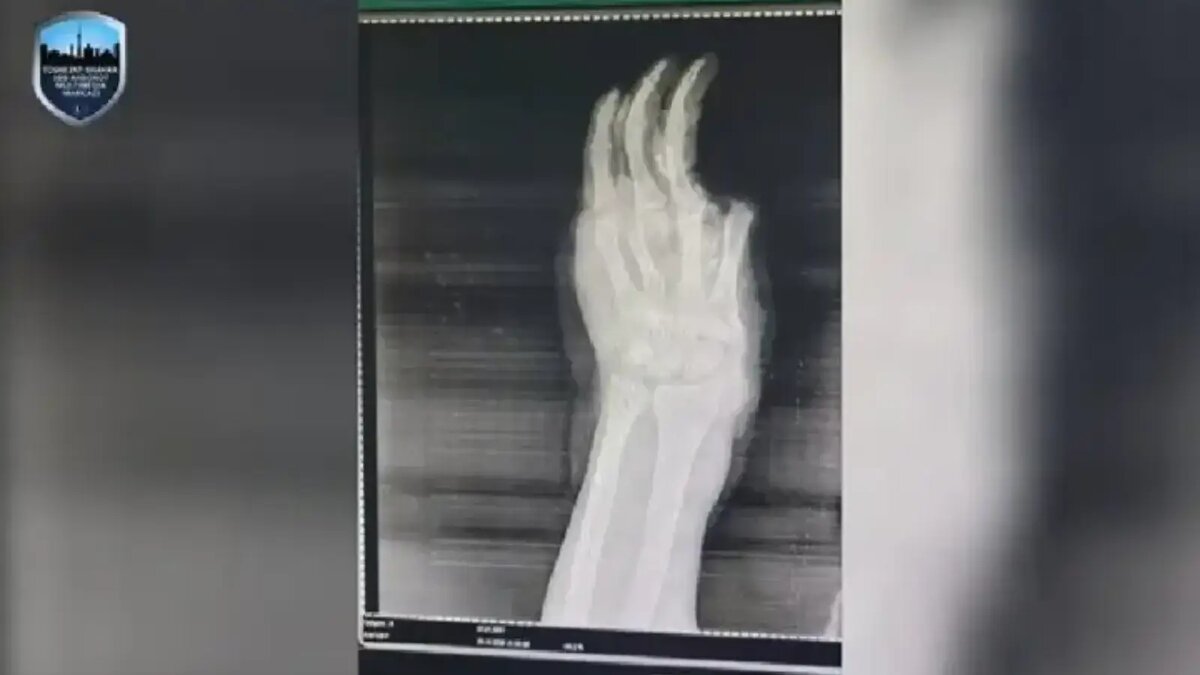

В Ташкенте взрыв пиротехники лишил ребёнка руки

Как отмечается, недавно в Республиканский научный центр экстренной медицинской помощи доставили ребёнка, проживающего в Янгихаётском районе, с тяжёлыми травмами. При первичном осмотре установлено, что пиротехническое изделие взорвалось у него в руке.

В результате взрыва у ребёнка зафиксированы ожоги в разных частях тела, а также оторвало несколько пальцев на травмированной руке. Самое тяжёлое — из‑за раздробления всех костей кисти и серьёзного повреждения тканей врачам пришлось ампутировать кисть.